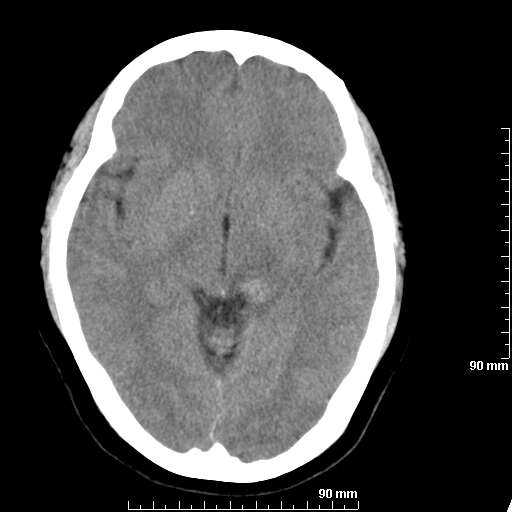

我院西门子单排CT由于一零件受损而产生的伪影.

哈哈,都不是。是虑线器fiter裂损。大家没想到吧。

哦,跟脑出血有点像哦

形状不规则,边缘模糊。比较特殊的一种伪影哈!

这种伪影很常见!伪影应该是在视野的中心的。

西门子的虑线器fiter裂损这才是很难见的问题,GE的最常见

虑线器老化,中间崩裂一块掉了